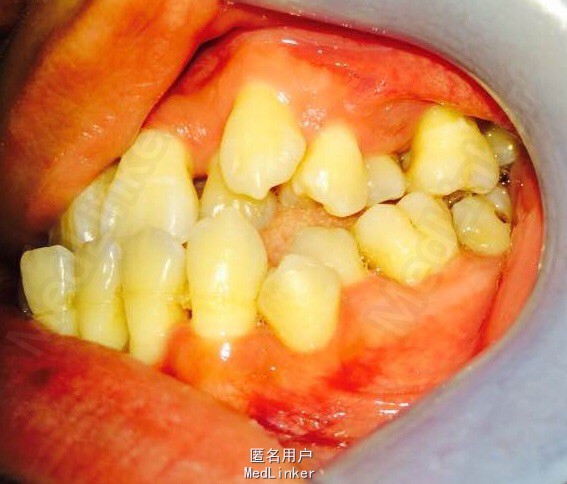

女,23岁,重度侵袭性牙周病,有家族遗传性

讨论: 牙周治疗处于维护稳定阶段,下合2—2牙槽骨吸收至根尖1/3水平,是否适合正畸? 下合前牙的保留问题?